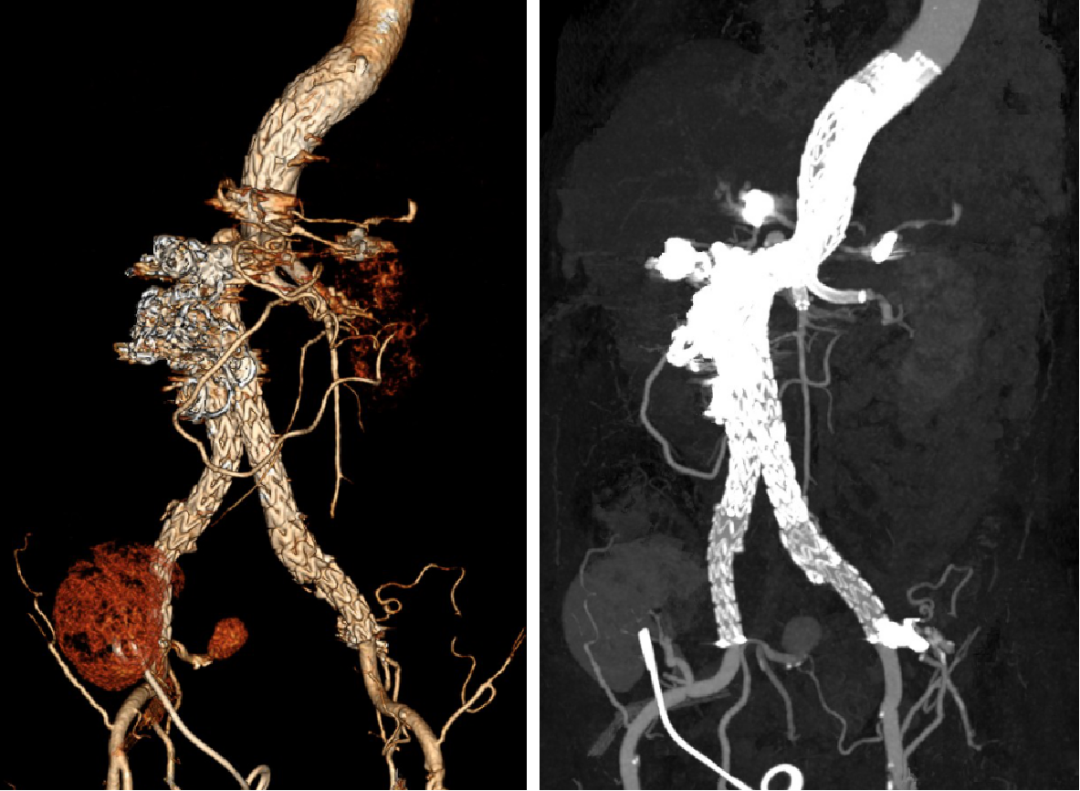

男性,38岁,双侧复杂性肾动脉瘤

03

肾周型腹主动脉瘤(瘤体累及双侧肾动脉)

男性,46岁

瘤体起于肠系膜上动脉开口下方,双侧肾动脉开口于瘤体

拟行双肾自体移植:右肾血管严重变异,无法重建,仅行左肾移植